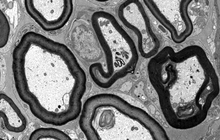

- Preparation of tissue sections for examination with a TEM microscope

On the other hand, in cutting-edge sciences such as tissue engineering, the use of up-to-date techniques for section preparation and cell tracking and engineered tissue structure has contributed significantly to the development of new studies.